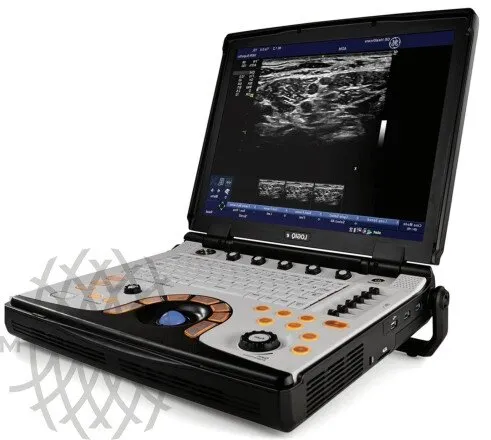

Портативный ультразвуковой аппарат GE Healthcare Logiq e

Особенности системы

УЗИ аппарат LOGIQ e — это высочайшее качество визуализации, настоящая универсальность и компактность. Обновленная версия системы — LOGIQ e R9 — обеспечивает ещё более высокий уровень качества изображений для более широкого спектра комплексных исследований, включая интраоперационные и малоинвазивные вмешательства. Аппарат составит достойную конкуренцию стационарным системам среднего и высокого класса, как в плане возможностей, так и цены.

Систему отличает наличие датчиков со сверхвысокими частотами сканирования, эталонная чувствительность доплеровских режимов для сосудистых исследований, в том числе наиболее сложных транскраниальных, а также высокая частота кадров, которая необходима для качественных кардиологических исследований.

Портативный ультразвуковой сканер Logiq e одинаково эффективно решает диагностические задачи при проведении абдоминальных, сосудистых, кардиологических, акушерско-гинекологических исследований и исследовании поверхностных органов. Позволяет легко работать с разными пациентами от новорожденных до взрослых с «лишним весом».

Небольшие габариты и малый вес системы позволяют легко использовать её на выезде. С другой стороны Logiq e может быть укомплектован тележкой с тремя активными портами для подключения датчиков, что позволяет полностью воспроизвести функционал полноценной стационарной системы для размещения в кабинете.

Некоторые характеристики консоли

- Масса 5 кг.

- Быстрая загрузка системы (менее 1 минуты).

- Встроенный жесткий диск типа SSD значительно увеличивает быстродействие и повышает безопасность системы при падениях.

- 3 порта USB для любых периферических устройств.

- Современный порт HDMI дает изображение высочайшего качества на внешнем мониторе.